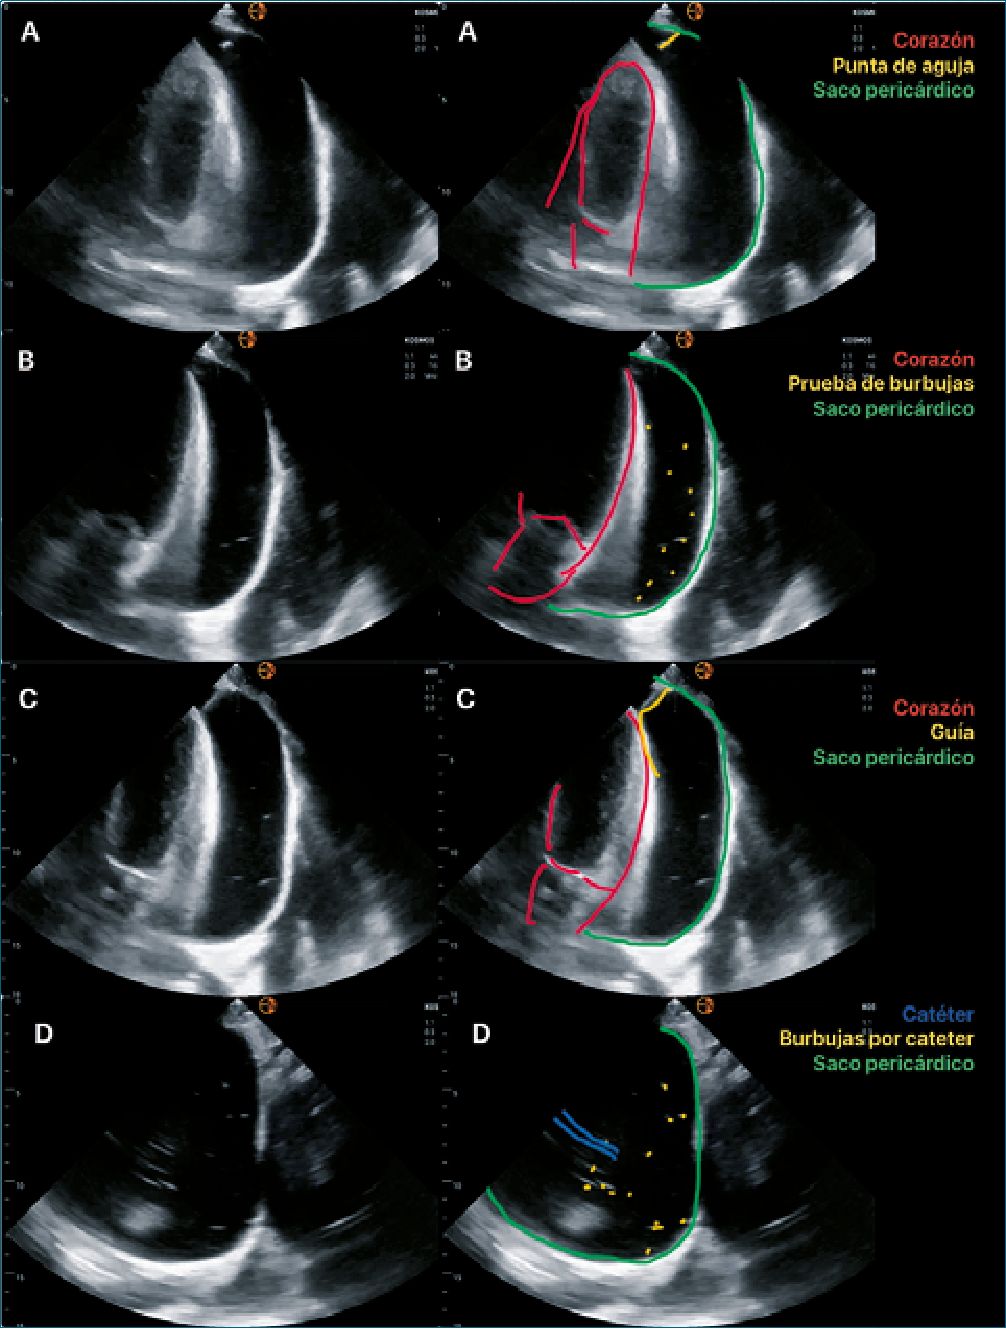

Figura 4. Técnica de pericardiocentesis. A: Introducción e identificación de punta de aguja; B: Prueba de burbujas verificación; C: Paso de guía; D: Catéter y burbujas, comprobación de ubicación.

2. Técnica (Figura 4)

• Una vez seleccionado el sitio de punción, realizando las medidas de prevención estándar, introducir la aguja paralela al haz de insonación, generando presión negativa con el émbolo de la jeringa, debemos ver en todo momento la punta de la aguja para disminuir la posibilidad de lesión de estructuras.

• Una vez obteniendo el líquido pericárdico en la jeringa, inyectar solución salina de tal manera que genere un contraste ecogénico con burbujas, las cuales deben ser visibles en el líquido pericárdico, comprobando la ubicación de la aguja[19].

sobre la cantidad mínima o máxima a drenar, nosotros tomamos en consideración la recomendación ATLS[20] acerca de realizar el drenaje de 70-100 ml de líquido pericárdico, posteriormente retirar la aguja y continuar con las compresiones, de otra manera al no resolver el taponamiento cardiaco, las compresiones serán inefectivas a pesar de la buena calidad de compresión externa. En situaciones diferentes a parada cardíaca, sugerimos colocar catéter para drenaje pericárdico. Por lo que, una vez comprobada la ubicación de la aguja, pasaremos la guía de catéter hasta ser visible en la ventana ecográfica, se corrobora la ubicación dentro del saco pericárdico y se retira la jeringa.

• Colocar dilatador.

• Colocar catéter vascular.

• Realizar nuevamente la prueba de burbujas, corroborando que el catéter se encuentra dentro del saco pericárdico.